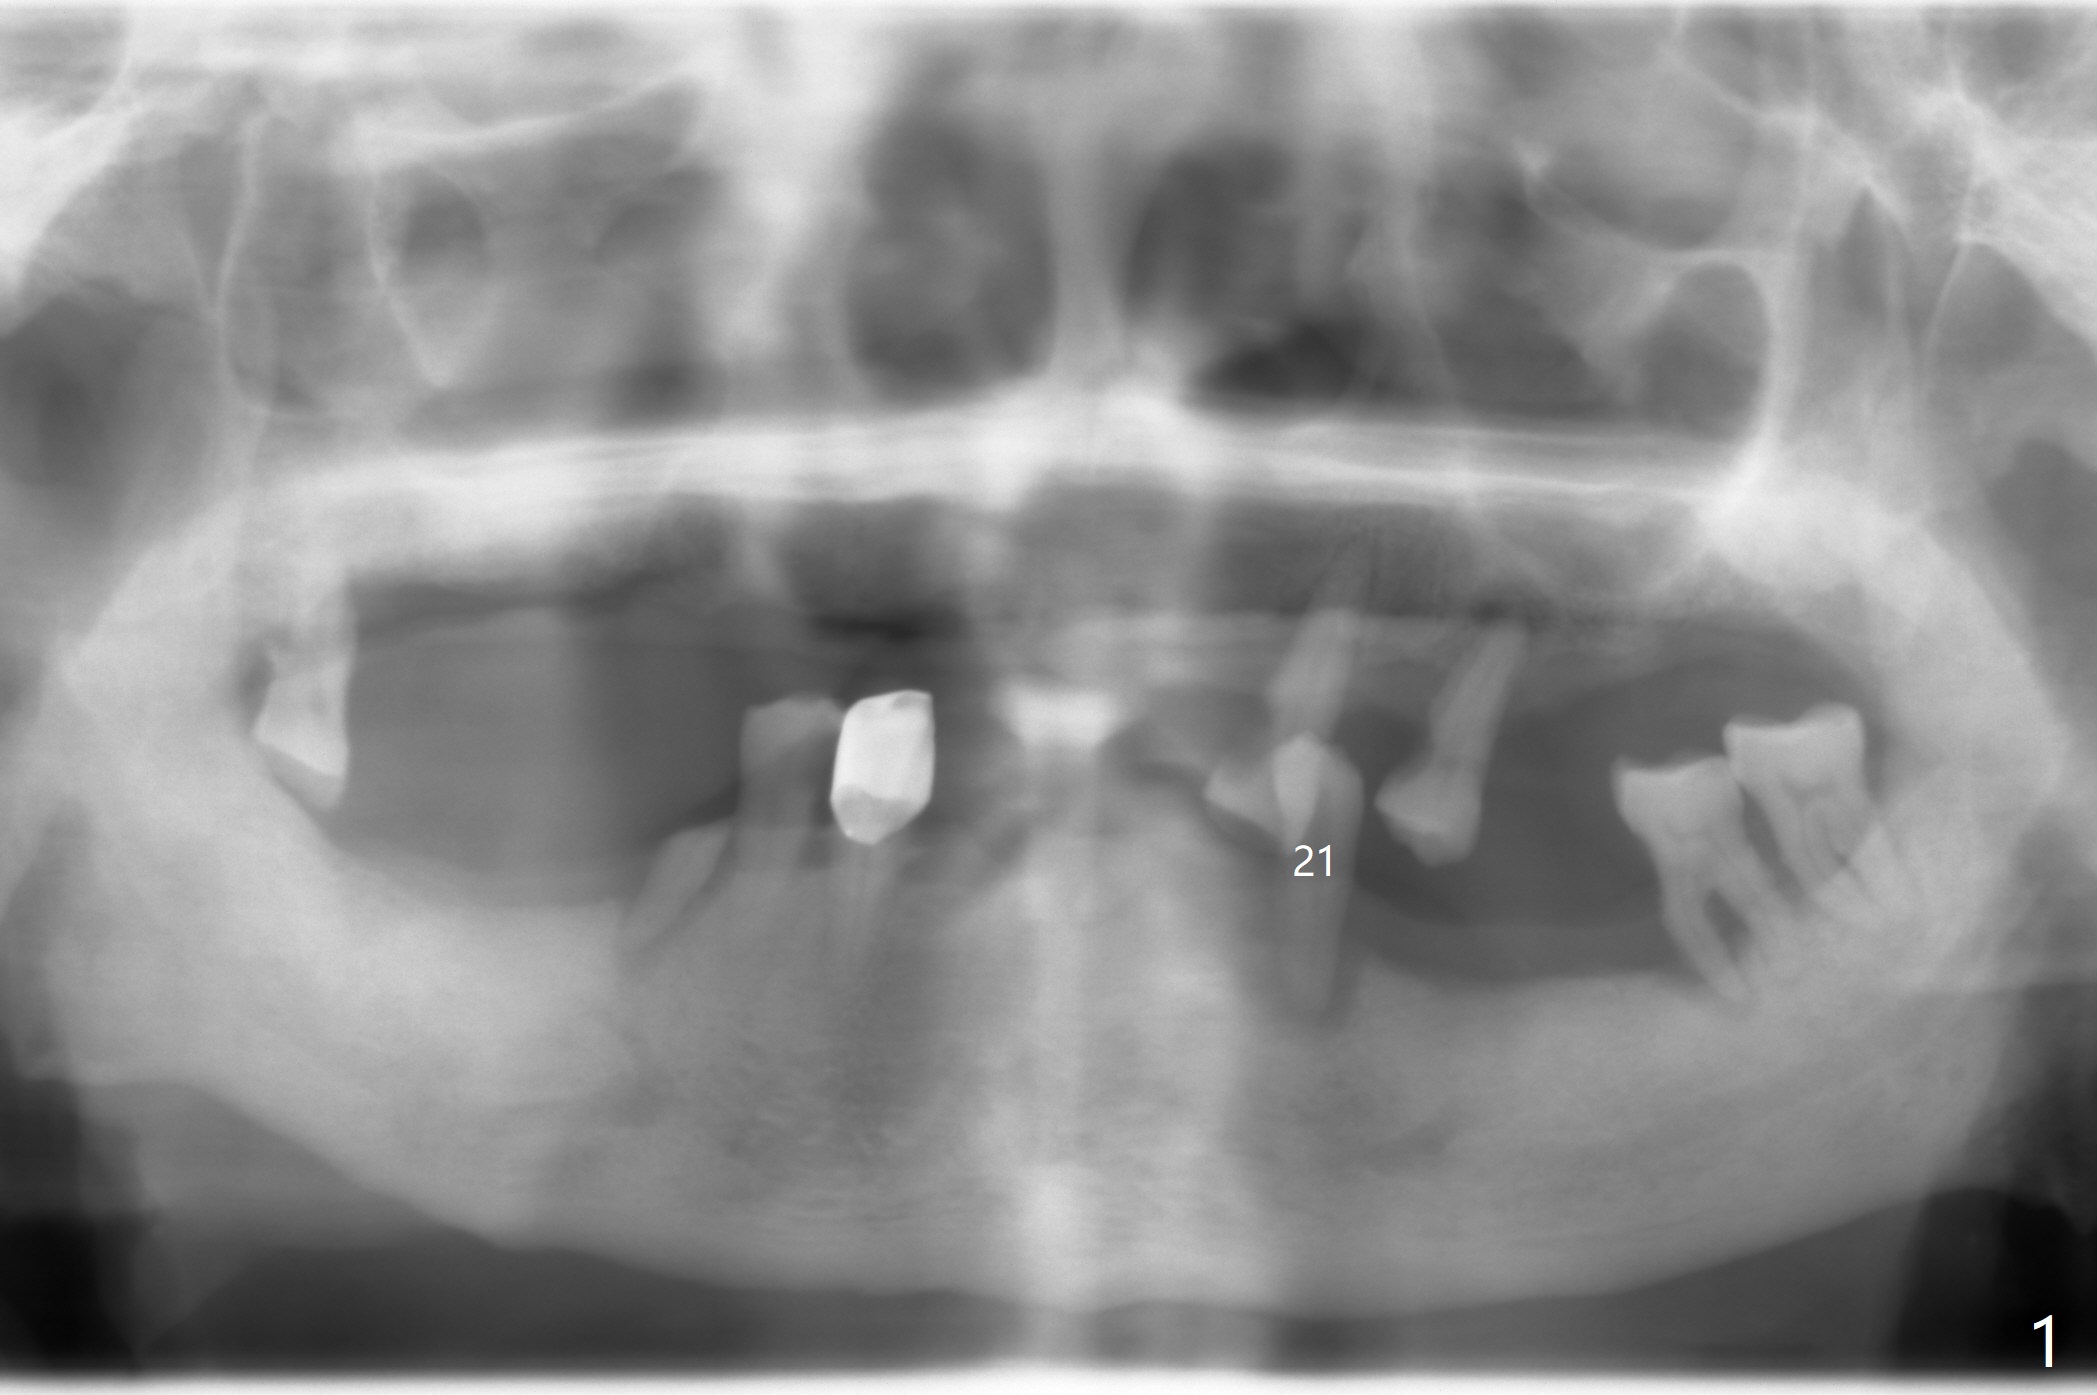

A 74-year-old man has RPDs to replace missing teeth (Fig.1). Recently the tooth #21 exfoliated. After placing 3.8x12 or 14 mm implant (Fig.2), a ball abutment is to be inserted (2 or 4 mm cuff). Truncate the root of the exfoliated tooth and use hard red acrylic to fixate the crown into the edentulous area of the lower RPD, leaving apical space for soft reline to provide the lightest RPD retention while the implant is osteointegrating. The soft reline can also solve food retention underneath RPD. When the implant heals, switch to hard reline and fixate a housing for the ball abutment. #15 blade will be needed to remove the higher mesial crest (Fig.2 white area) so that the latter will be even the distal one (*). Last identify 3 vital structures associated with the surgery (Fig.2: yellow, red and pink dashed lines). What will happen if each one of them gets injured?